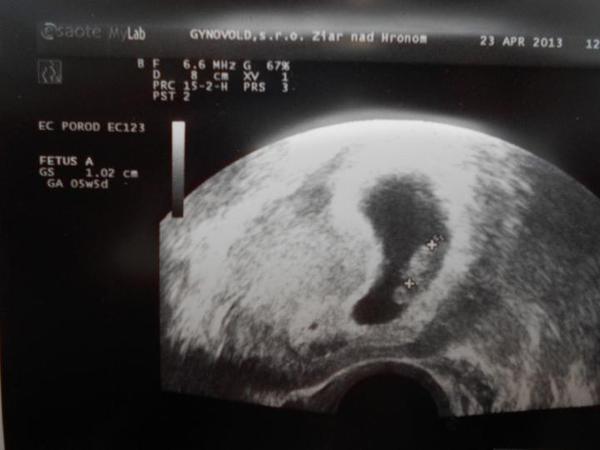

Baby, uz ste setky boli na ultrazvuku? A bolo nieco vidiet? Som trochu nesvoja, dnes som bola na pohotovosti kvoli spineniu a bolo vidiet iba bublinku, ani zlte teliesko, nic a to koncim 7 tt 😐😕😔 tak som z toho smutna 😔😔😔😔😔 este som si povedala, ze mozno zalezi od stroja....

@14nunu10 ano, aj mi napadlo, ze to tak nejak bude. no je fajn, ze to vobec vidno., asi kazdy dr. nema take sono, aby to takto dokladne zobrazil, teda aspon myslim. neviem, lebo z predosleho tehu takuto foto nemam. dr. som vzdy musela ziadat, aby mi urobil snimku. no takze aj ty este na foto cakas. ja mam noveho dr. a vraj je celkom fajn, tak uvidime, ako sa o nas bude starat.

@rbabulka urcite zalezi od sona. niektori dr. maju urcite stare pristroje. niekedy moze byt aj ovulka posunuta a preto je babo este moc malicke, aby sa pekne zobrazovalo. a spinenie? ja som pri predoslom tehu mala v 7-8tt tiez, najskor svetlohnedy vytok, potom presiel do tmaveho, tak ma dr. nechal na PN. o 3t som mala kontrolu. den pred kontrolou som bola na wc - mala som zapchu, tak to bolo trochu narocnejsie a spustilo sa mi krvacanie - cerstva krv. na druhy den uz iba trochu, potom ustalo. dr. ma zakazdym kontroloval a vyzdy bolo vsetko OK. a vysledok tehu mam doma a ma 5,5r. 🙂